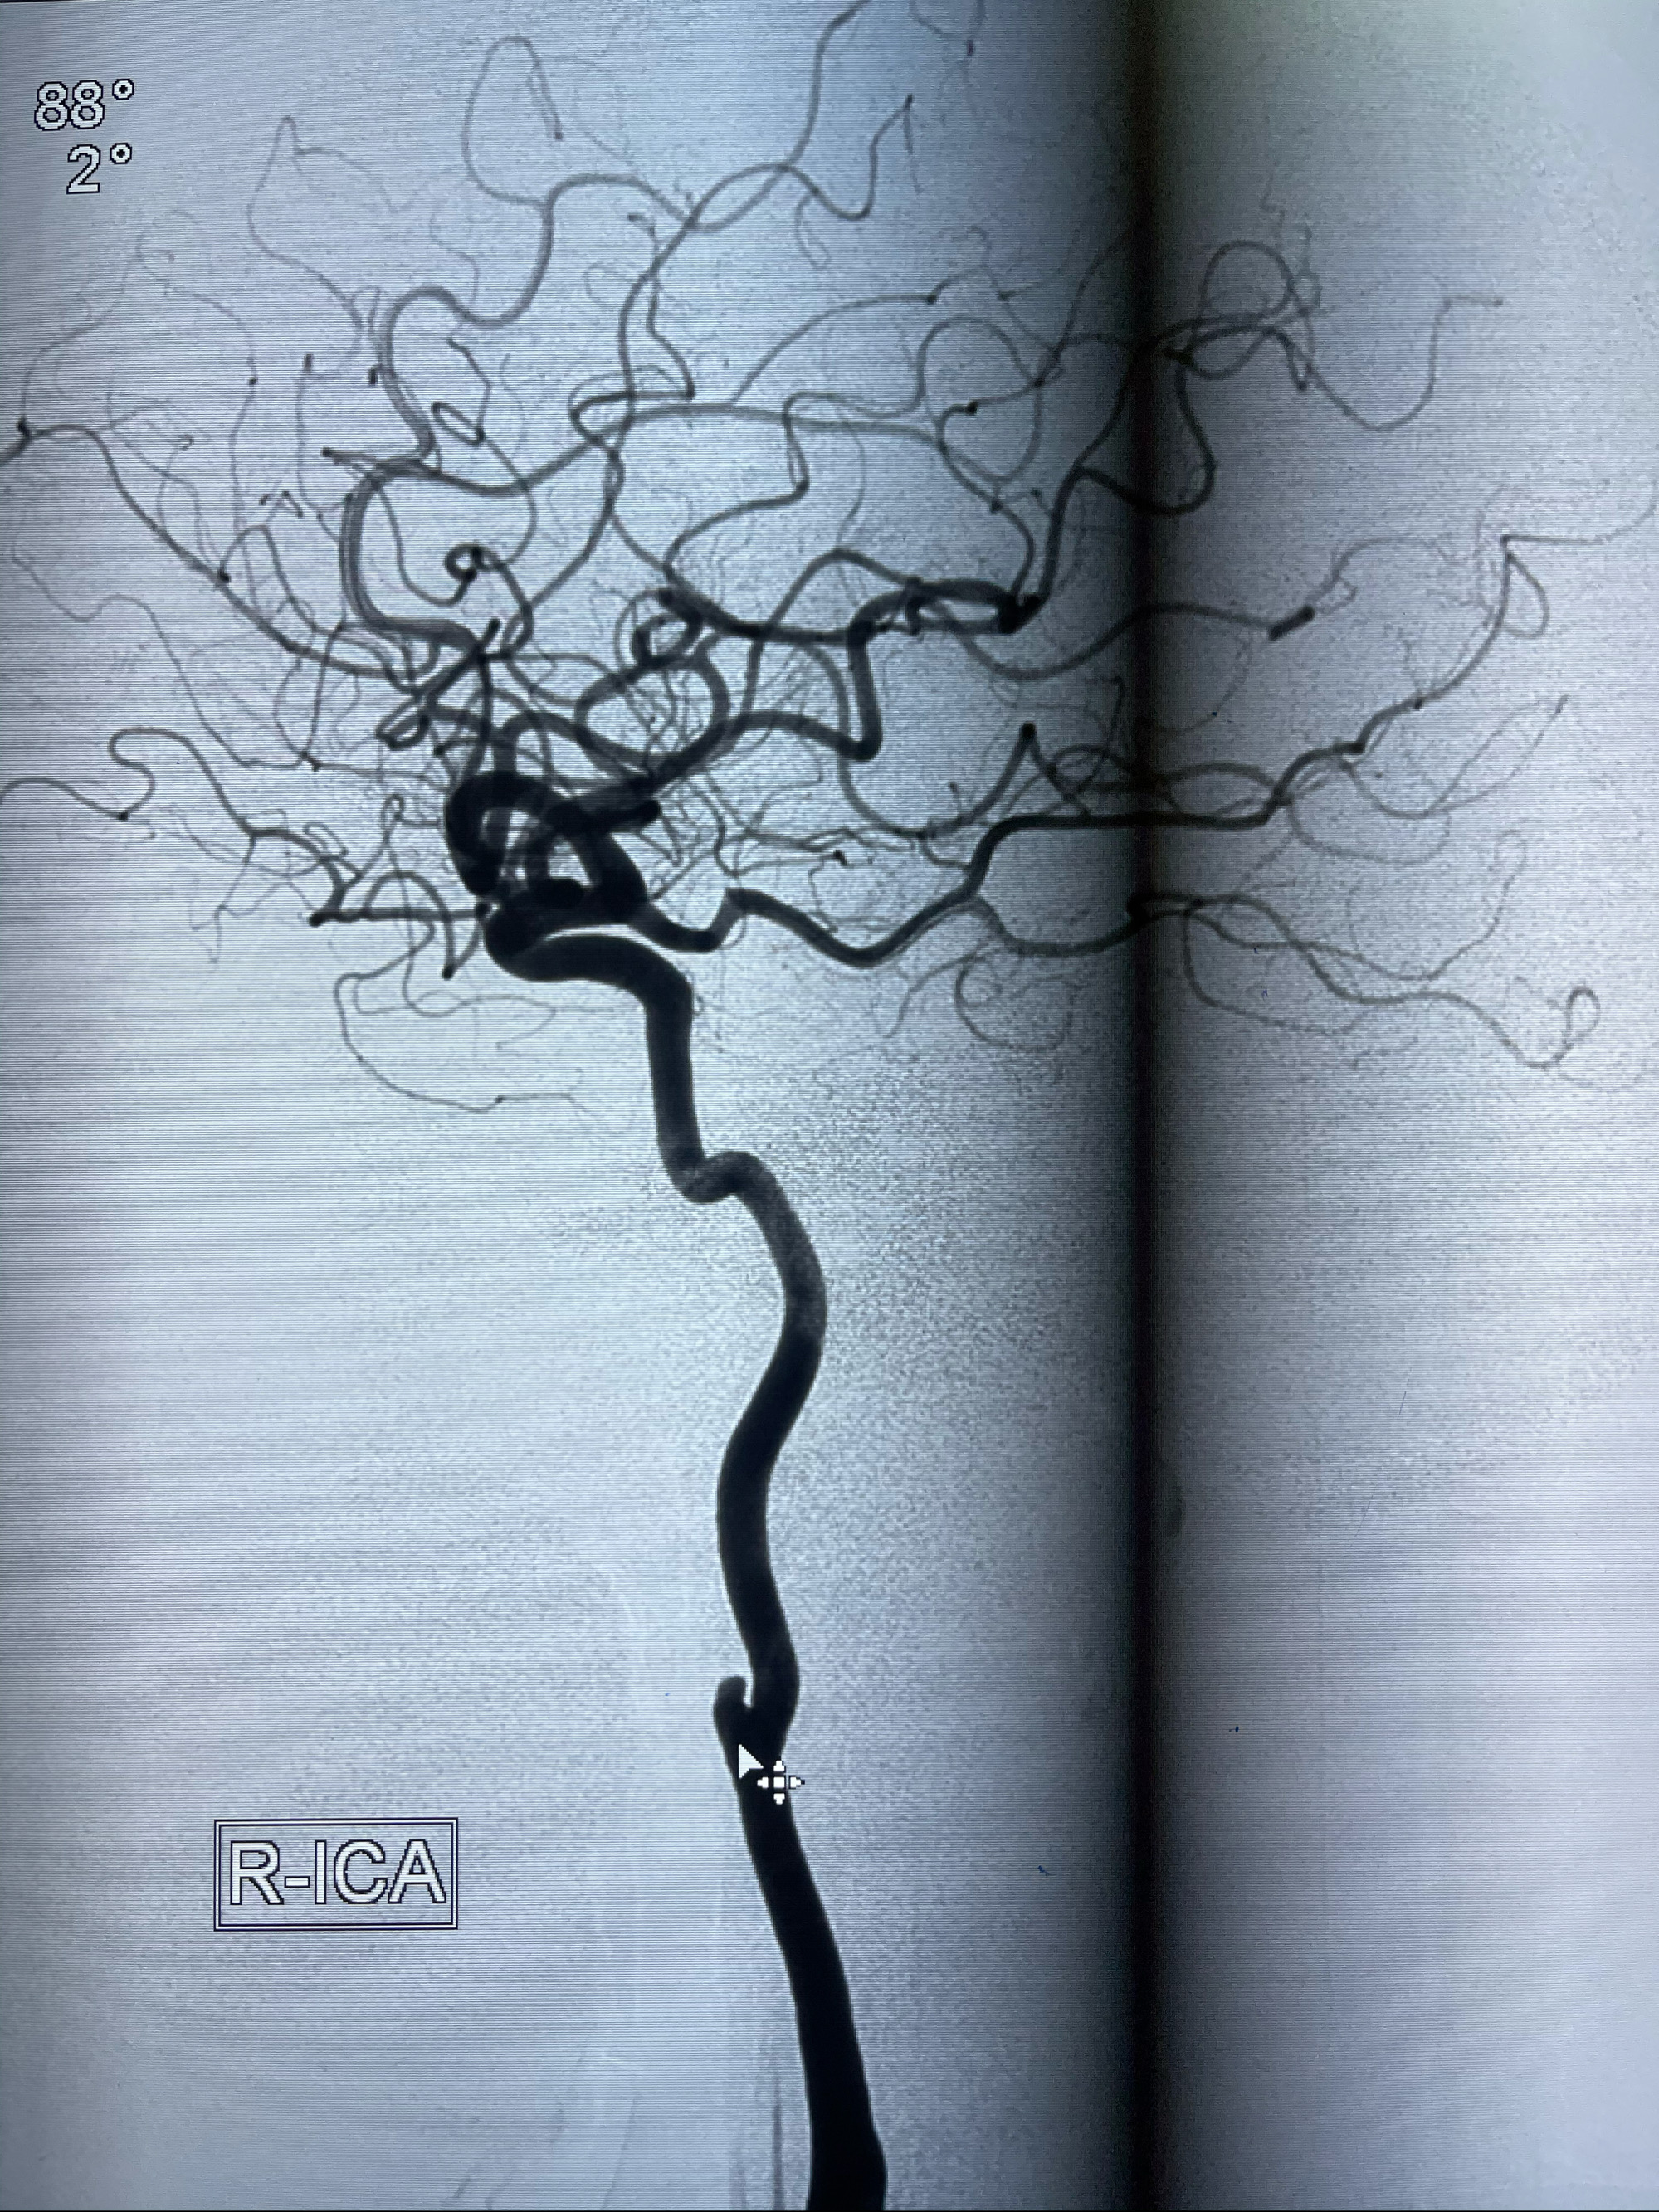

2021-03-08行全脑血管造影

1.右侧颈内动脉夹层动脉瘤Lvis支架辅助;

右侧颈内动脉夹层动脉瘤Lvis5.5-20mm支架辅助栓塞

工作角度造影